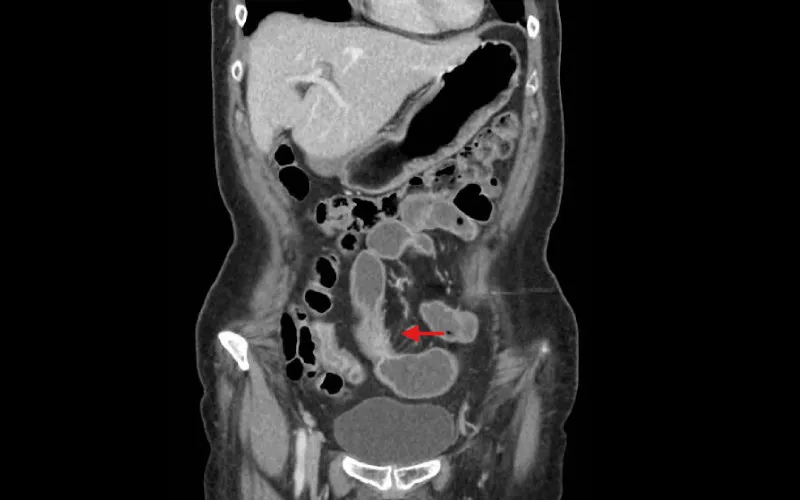

CT imaging showing fatty tissue

CT imaging showing thickened and fibrous fatty tissue around the small intestine.

Dr. Kiran: Prior to her surgery, we performed a CT enterography, which showed abnormal appearance of the mid-small bowel, concerning for inflammatory bowel disease (IBD) but atypical for Crohn’s disease because of the apparent sparing of the terminal ileum.